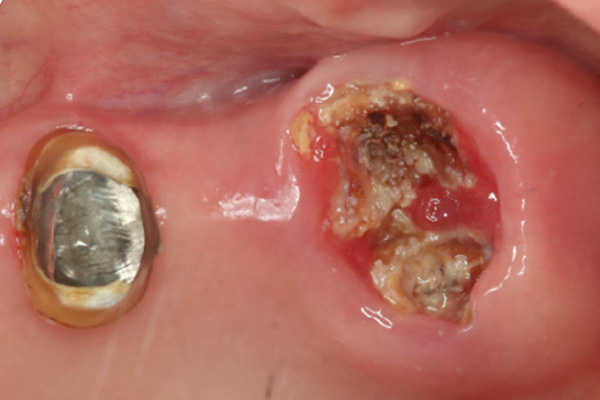

| 年代・性別 | 50代 男性 |

|---|---|

| 主訴 | 右下の歯が割れてしまったのでインプラントをして欲しい |

| 治療期間 | 約6ヶ月 |

| 費用 | 1,100,000円 |

| 治療内容 | インプラント、骨造成、結合組織移植、セラミック修復 |

| 治療に伴うリスク | インプラント周囲炎 セラミックの破折、脱離 |